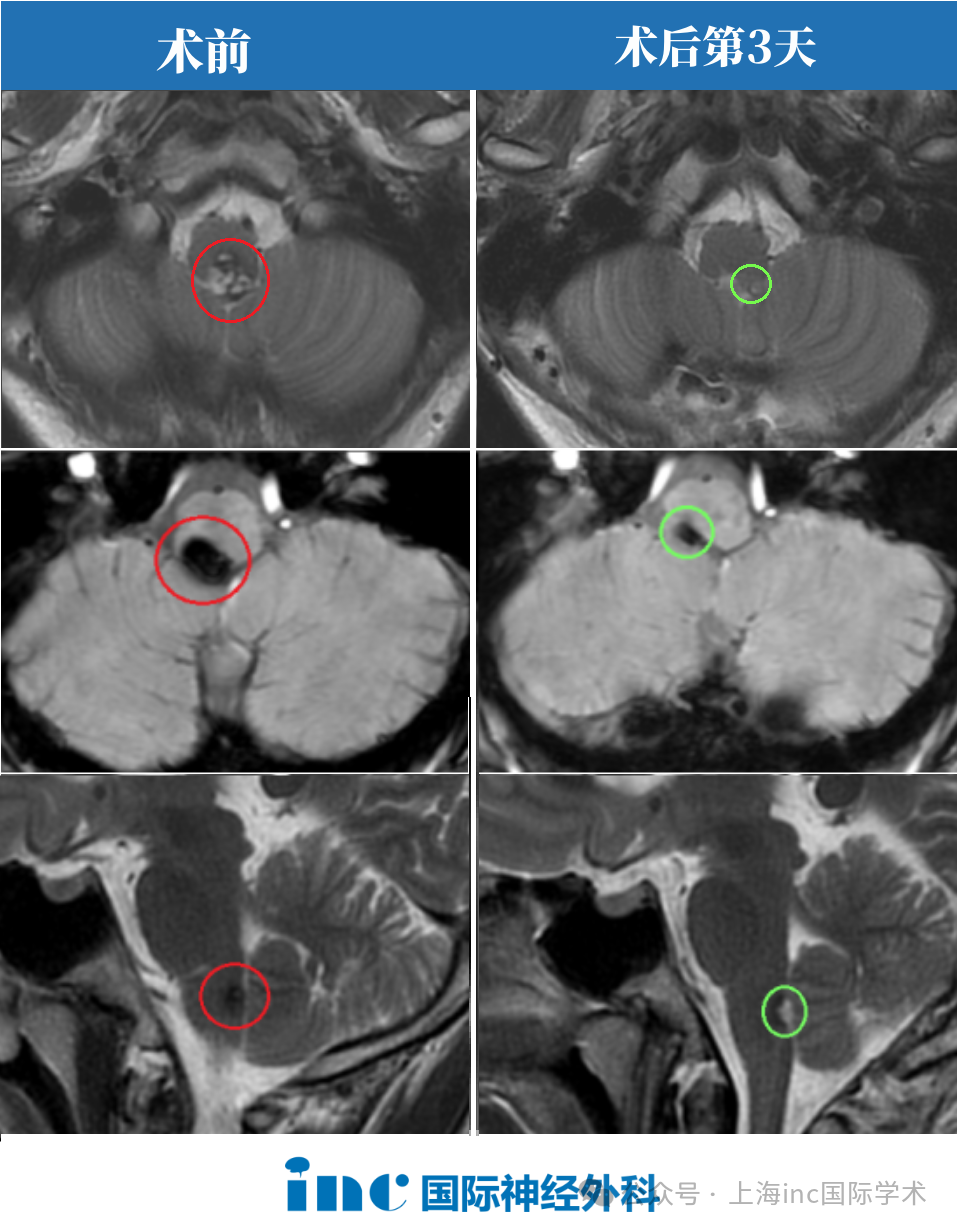

王先生在20岁时确诊了脑干海绵状血管瘤,在后来的日子里反复出血,逐渐演变到了视力下降、肢体无力麻木严重影响生活,一直到60岁才接受了由巴教授亲自主刀的脑干海绵状血管瘤切除术,终于将导致王先生反复出血的脑干海绵状血管瘤病灶进行全切。术后第三天就可下床活动,无新发神经功能损伤,术后两周出院。

INC德国巴特朗菲教授于2021年5月来华疑难手术示范。5月21日,60岁的王先生在苏州大学附属第四医院接受了由“巴教授”亲自主刀的脑干海绵状血管瘤切除术。导致王先生反复出血的脑干海绵状血管瘤病灶得到全切,王先生术后第二天就转出了ICU,术后第三天就可下床活动,可正常进食,无新发神经功能损伤,术后两周出院。